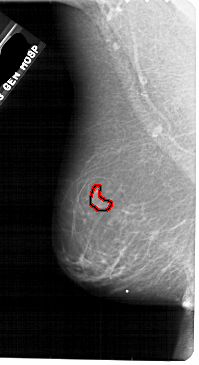

A_1884_1.LEFT_CC

LEFT_CC LINES 5356 PIXELS_PER_LINE 2986 BITS_PER_PIXEL 12 RESOLUTION 43.5 OVERLAY

FILE: A_1884_1.LEFT_CC.OVERLAY

TOTAL_ABNORMALITIES 1

ABNORMALITY 1

LESION_TYPE MASS SHAPE LOBULATED MARGINS OBSCURED

ASSESSMENT 4

SUBTLETY 3

PATHOLOGY BENIGN

TOTAL_OUTLINES 1

BOUNDARY